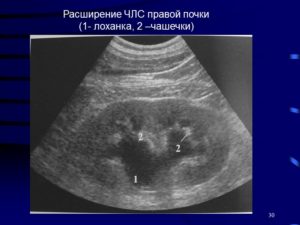

Основной метод диагностики – ультразвуковое исследование (УЗИ). Неосложненная пиелоэктазия в лечении не нуждается. Прогноз зависит от причинного заболевания и состояния здоровья пациента.

Ультразвуковое исследование – очень эффективный метод скрининга. Однако УЗИ недостаточно для определения степени расстройства мочевого транспорта и функции пораженной почки. Необходимы дальнейшие диагностические процедуры.

Рекомендуется провести почечную сцинтиграфию, а в редких случаях – точно визуализировать анатомию с магнитно-резонансной томографией. Расширение ЧЛС правой почки быстро выявляется с помощью УЗИ.